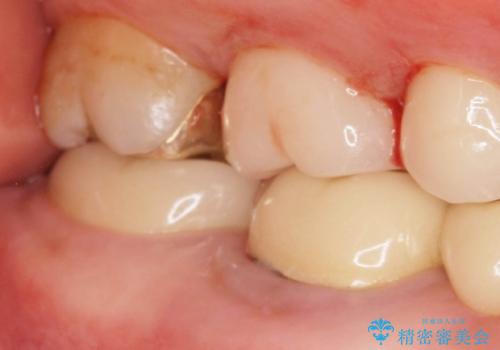

インレー下に再発した虫歯 セラミッククラウンによるやり替え

- 「食事の際にバキッと音がした。心配なので見てほしい。」と歯の検診を希望され来院されました。

視診にて、インレーの破折、インレー下に虫歯が再発していることを認めました。

壊れてしまったインレーおよび、虫歯を神経を温存できるよう丁寧に除去したのち、耐破折に優れるセラミッククラウンで再補綴治療を行います。

再発した虫歯は小さくなかったものの、丁寧に虫歯をとることで神経を温存することができました。